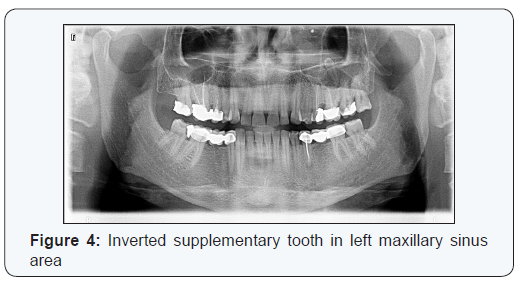

A 36 year old systemically healthy Caucasian male patient was referred to Istanbul University Oral and Maxillofacial Radiology Department for pain at 27 number teeth. Intraoral examination revealed carious cavities at 14, 27, 38. Patient’s panoramic radiography showed an inverted extra tooth (Figure4). Because of its normal morphology the tooth was considered as supplemental ectopic tooth. Deficient root canal treatment at 15, overfilled root canal treatment at 16 teeth, apical lesions at 25, 35 were also observed in panoramic radiography. Cone beam computerized tomography(CBCT) was to assess the exact location of the tooth and its relation with peripheral tissues. Tomographic images showed that the tooth was located inside the sinus and nasal cavity partially. Only root of the ectopic tooth was surrounded by sinus mucosa locally and tip of the crown was located inside nasal cavity (Figure 5). Since the patient didn’t have any symptoms like sinusitis, foul odor, no surgery was planned and patient was called for control examinations.